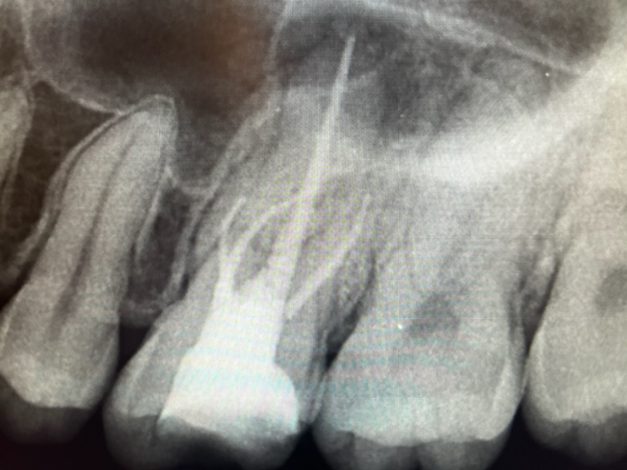

専門医による歯内療法🦷

州デンタルオフィスでは、専門医による歯内療法を行っています 現在では他院の患者様も多数ご紹介頂くことが多くなりました 根管治療はなんどもおこなうことができません その為、できるだけ初期の段階で…